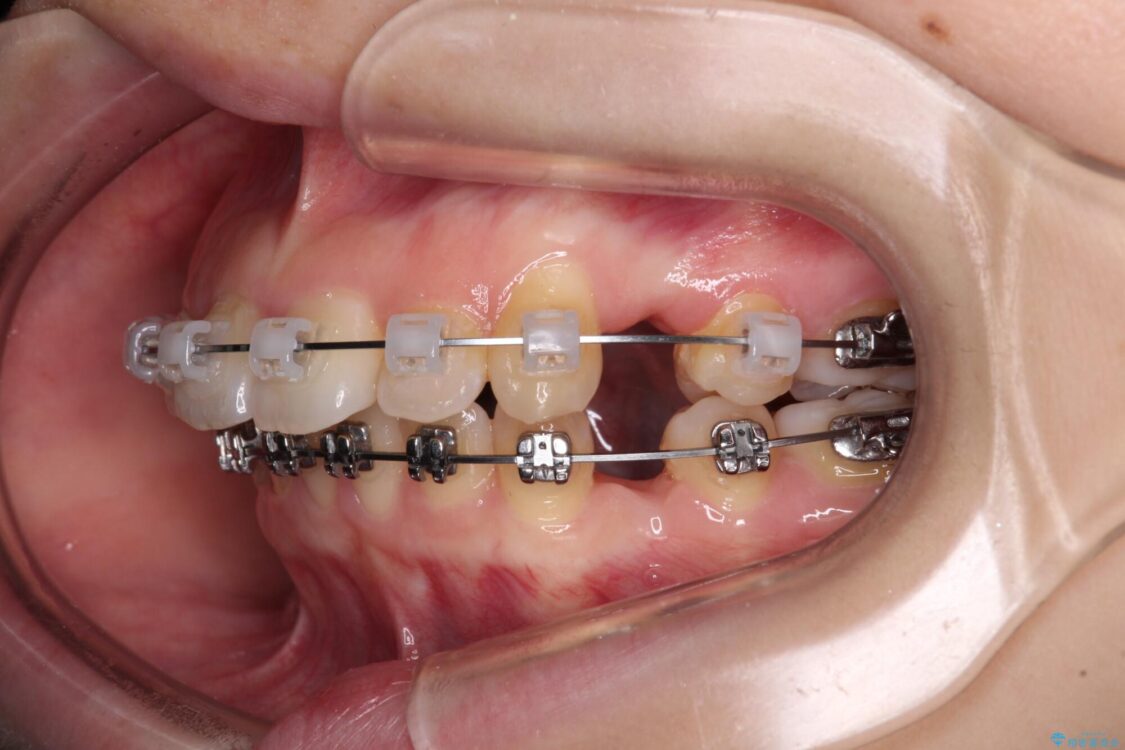

治療途中

• 【モニター】口が閉じられない ワイヤー装置での抜歯矯正 治療途中画像

※写真にある上顎装置はメタルブラケットではありません。メーカー在庫都合などにより別の装置を使用しております。

上下前歯が著しく前突している状態であったので、上下左右の第1小臼歯4本を抜歯し、ワイヤー装置にて矯正治療を行うこととしました。